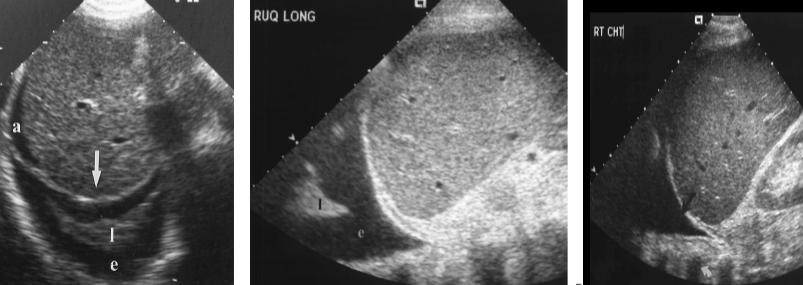

trauma

subcapsular hematoma

intraparenchymal hematoma

liver transplant

pleural effusion

post-op fluid collection (ascites and pleural effusion)

portal hypertension

collaterals/varices/cavernous transformation